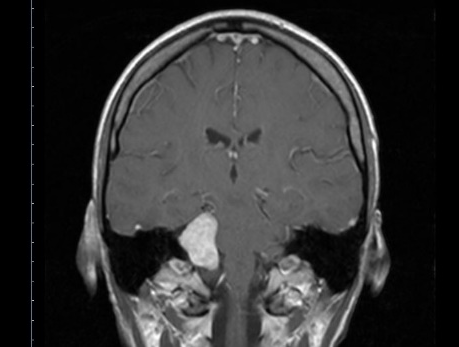

I was diagnosed with a large Vestibular Schwannoma brain tumour in September 2023. I’d had many years of symptoms including numbness of my face, balance issues and vertigo. For almost 3 years I went to doctors, yet my symptoms were ignored and I was told it was mental health related. It was my dentist who finally sent me for a scan.

When I was diagnosed and heard the words benign, I felt relief, as my husband and I have four young children and I needed to be around for them.

I had surgery to remove the tumour in April 2024, and after 14 hours on the operating table my husband received the call to tell him the surgery went well… Less than one hour later he got another call saying I hadn’t woken up and was going straight for a scan.

What they found then was a huge clot pressing on my brain stem. It totally blindsided everyone, even the professionals. They actually ended up getting a few neurosurgeons from London involved too. I think there were 5 in total. “It’s a very rare case” they said.